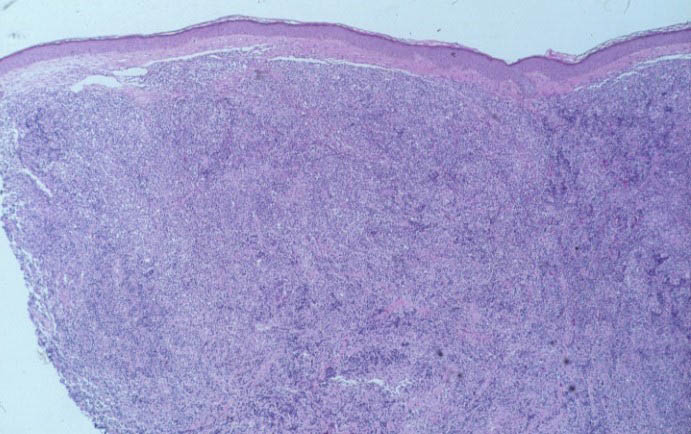

Atlas of skin histopathology

Purple nodule = عقيدة ارجوانية